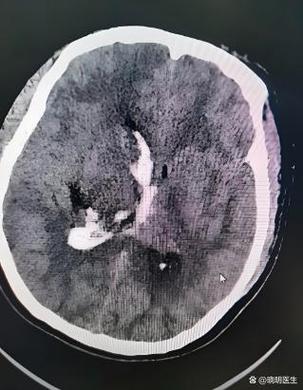

- 什么是腔隙性? 这种梗死灶非常小,通常直径在1.5-3毫米之间,它发生在大脑深部的一些特殊小动脉供血的区域,这些小动脉像树枝的末梢,一旦堵塞,影响的范围就很小,形成一个“腔隙”样的病灶。

- 腔梗是缺血灶的一种,腔梗是已经发生了坏死的、陈旧的缺血灶,在影像上表现为一个明确的“小洞”。

- 白质变性:大脑内部负责连接不同神经纤维的“白质”会出现一些轻微的缺血性改变,在影像上表现为一些片状的、边界不清的信号异常,这和脑小血管病有关。